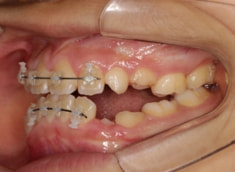

治療後(1年5ヶ月後)

治療開始から11ヶ月